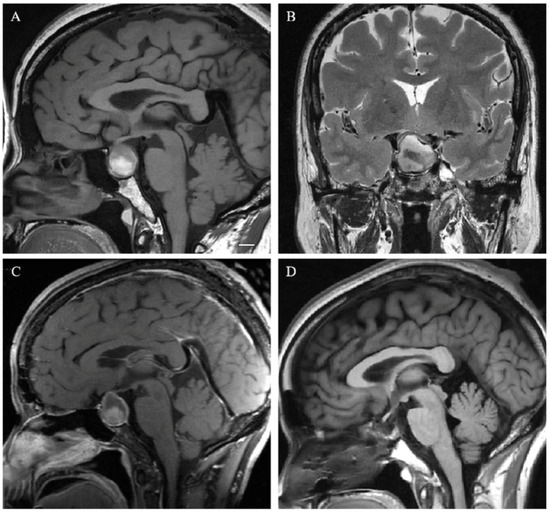

2.3. Neuroradiological Evaluation

3.2. Neuroradiological Features